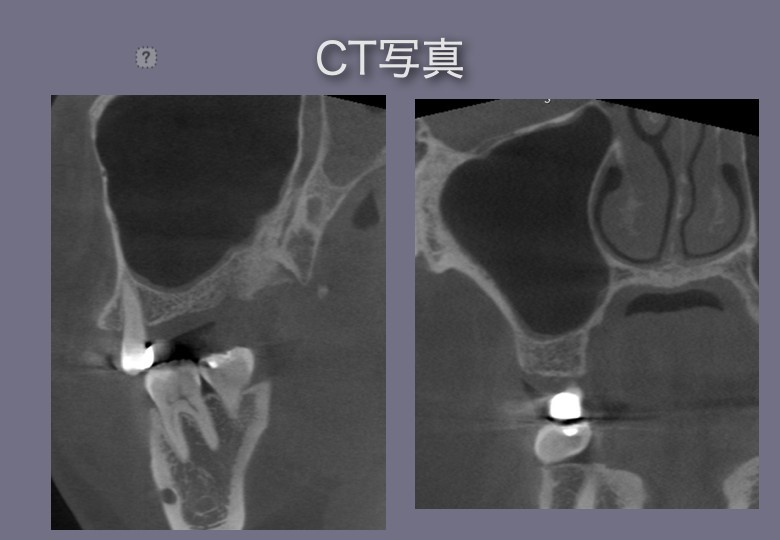

以下、実際の症例です

サイナスリフト・クレスタルアプローチ

インプラント前

インプラント後

サイナスリフト・ラテラルアプローチ

今ある骨の外側につくる方法

骨造成=GBR(骨再生誘導法)Guided Bone Regeneration

今ある骨の内側につくる方法

サイナスリフト(ラテラルアプローチ・クレスタルアプローチ)

を同時にしているインプラント治療症例です